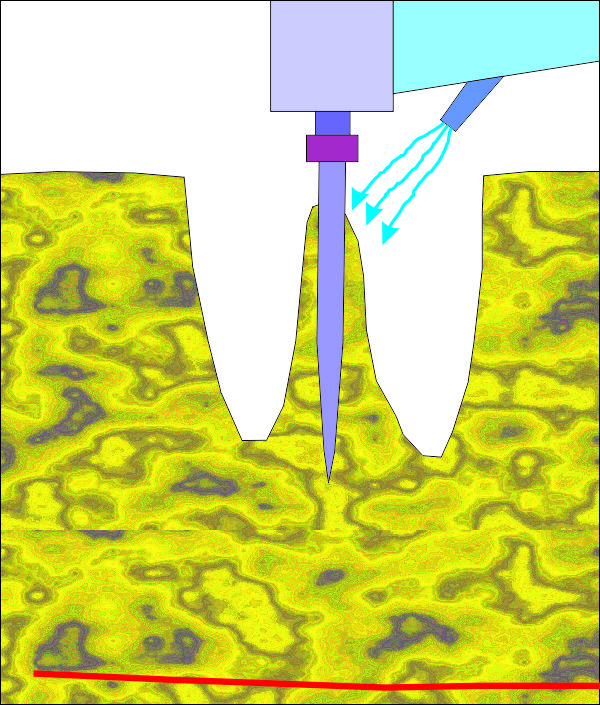

Първоначално разпробиване за имедиатно поставяне на зъбен имплант след

екстракция на долен молар. При горните моларни зъби ситуацията е идентична, но

има три корена вместо два. Идеята е да се центрова пилотната фреза в центъра на

интеррадикуларната септа, при което да се получи оптимално позициониране на

импланта. В много случаи фрезата се приплъзва встрани и започва да пробива във

възможно най-неудачното направление, така че е добре тя да се държи стабилно от

оператора, особено в началото. Добрите пилотни фрези имат силно заострен връх,

който е възможно да бъде поставен в една точка и да не се приплъзва встрани -

дори и при остра септа. При наличие на пародонтален проблем горната част на

преградата е резорбирана и фиксацията на фрезата е технически много по-лесна.

При употребата на

хирургичен водач определянето на правилната посока на разпробиване също е

доста по-лесно.

Какво се случва в костта при поставяне на

зъбни

импланти? Това е една графична схема на процесите, които се наблюдават в

костта за период от няколко месеца. При зъбните импланти се говори за

първична и вторична стабилност - първичната се определя от механични фактори

(дизайнът на импланта), а вторичната - основно от биологични фактори

(имплантатната повърхност, заздравителните процеси в костта, обмяната и

храненето на периимплантатната кост и меките тъкани и много други). Все пак

дори и тези принципи не са валидни на 100 % - дизайнът на импланта има

значение за вторичната стабилност, а качеството на костта и имплантатната

повърхност също играят роля за първичната стабилност на импланта. Първична е

стабилността през първите няколко месеца, а вторична - след приключването на

остеоинтеграцията. На горната схема с червена линия е означена

първичната стабилност, а със синя - вторичната. И двата типа стабилност се

измерват в проценти, като за измерване се използва апаратът

Ostell, който излъчва ултразвукови вълни и измерва

доколко имплантатът е срастнал с костта. При 100 % измерена стойност има

пълна

остеоинтеграция, а при 0 % - пълен провал в лечението. Характерно за

първичната стабилност е намаляването на стойността с течение на времето -

поради компресия на костта, влошено хранене, прогресираща костна резорбция и

т.н. фактори. Обратно, с течение на времето вторичната стабилност нараства -

поради синтез на нова костна тъкан, минерализация и добре протичащи

оздравителни процеси. Сумарната имплантатна стабилност е означена със зелена

линия на горната графика - тя е резултат от наслагването на линията на

първичната и вторичната стабилност. Вижда се едно хлътване през периода от

четвъртата до шестата седмица - това е т.нар. критичен период, през който

има опасност от провал в имплантатното лечение и не е добре да се натоварва

имплантатът - или се натоварва рано, или отсрочено, през четвърти - шести

месец. Повечето автори са единодушни че около шестия месец остеоинтеграцията

вече е приключила. Повечето

съвременни имплантатни системи се стремят към

идеалния случай - черната линия, при който критичен период липсва и

имплантатната стабилност е постоянна, близо до 100 %. Все пак от медицинска

гледна точка стойности от порядъка на сто процента се постигат изключително

рядко - в идеалния случай, добрите имплантатни системи би следвало да

следват линията, означена с кафяво на горната графика - хлътването е съвсем

минимално. Такъв клиничен резултат е напълно постижим - чрез подобряване на

формата на импланта и неговата повърхност, което е резултат на доста

проучвания и непрекъснато усъвършенстване на зъбните импланти. Така например

при много съвременни имплантатни ситеми се говори за концепцията

any time loading - натоварване по всяко време без

да се съобразяваме с критичния период. В действителност, при

класическото имедиатно натоварване до 48 часа след поставяне на импланта

зелената крива губи своето значение - преди хлътването имплантатът вече е

натоварен и, както стана въпрос по-горе, остеогенезата се стимулира.

Критичният период при тези условия няма да се усети по никакъв начин. Дори

според доста автори при по-голям по размер имплант няма нужда и от шиниране

на изработената корона; при имплантатен блок пък сигурността е още